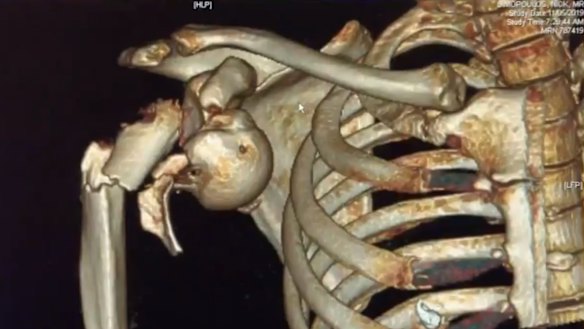

A medical scan showing Nik Dimopoulos' injuries.

It was the wrong property and Mr Dimopoulos, who was incorrectly identified as the offender, received multiple fractures to his arm when it was pulled from his shoulder socket during the arrest.

The surgeon who operated on Mr Dimopoulos has described it as one of the worst shoulder fractures he had ever seen.